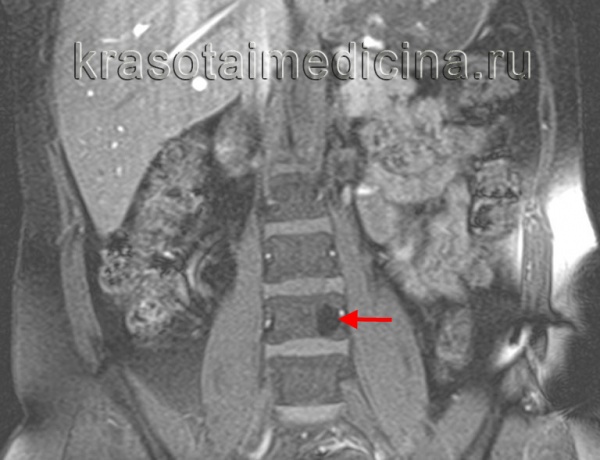

(Слева) На аксиальной КТ без КУ визуализируется относительно хорошо отграниченный участок без склеротического ободка. Ключевые диагностические признаки: «жировая» плотность и картина «пчелиных сот».

(Справа) На сагиттальной реформатированной КТ определяется гиподенсный участок в теле СЗ с немногочисленными утолщенными трабекулами, ориентированными вертикально (характерные КТ-признаки гемангиомы позвонка). Вертикальные трабекулы не всегда соединяют обе замы кегельные пластинки.

(Слева) На аксиальной МРТ (Т2 ВИ) отчетливо определяются ожидаемые признаки гемангиомы позвонка. В изоинтенсивном объемном образовании ограниченным телом позвонка, визуализируются трабекулы и жировая ткань.

(Справа) На сагиттальной MPT (STIR) определяется полное подавление сигнала в типичной гемангиоме, целиком представленной жировой тканью. Картина гемангиомы на Т2 ВИ вариабельна и зависит от жировых и сосудистых элементов.